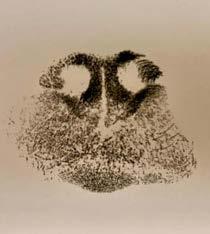

This case is a cutaneous poorly pigmented melanoma. The cytologic appearance of the cells is very similar to a histiocytoma but there are two key (but subtle) differences. Firstly, some of the cells contain a fine dusting of green pigment in the cytoplasm which is consistent with melanin. This is not expected with a histiocytoma but is expected in a melanoma, melanocytoma or pigmented epithelial cell tumour. The cells being round and not cohesive makes epithelial origin unlikely. Secondly, the nuceloli are prominent in these cells and sometimes quite large which is not expected with a histiocytoma nor a melanocytoma, but is a characteristic feature of melanoma (which is a malignant tumour).

Cytology description: The cytology is highly cellular with good cell preservation and staining, containing round cells amidst small amounts of blood in a light blue proteinaceous background. The round cells have round nuclei of granular chromatin with 1-3 prominent nucleoli and small to moderate amount of light blue cytoplasm often containing a few fine vacuoles and rarely containing a dusting of fine green pigment ( Figure 2 green arrows). They show marked anisokaryosis and anisocytosis (3-fold variation), variable nucleolar size and shape, frequent macronucleoli ( Figure 3 red arrow), variable N:C ratio, occasional binucleation and occasional mitoses are evident ( Figure 3 yellow arrow).

Interpretation: Melanocytic neoplasm, most likely malignant melanoma.